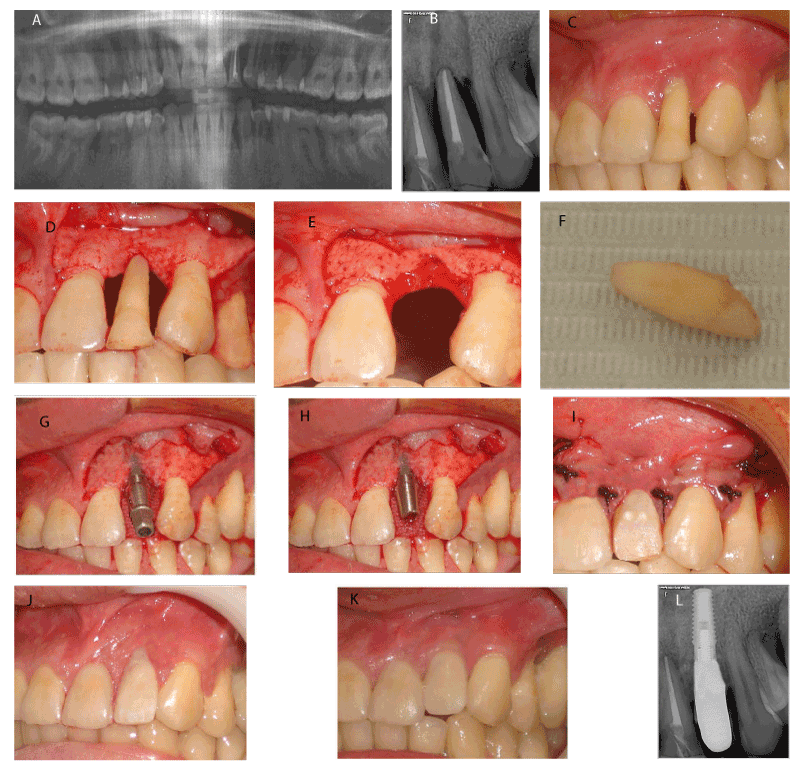

| Figure 1: Immediate implants without Duo-Teck membrane a) Preoperative O.P.G. b) Preoperative periapical x-ray c) Preoperative study cast. d) Clear acrylic splint. e) Preoperative view. f) Flap reflection g) Extraction of the involved tooth. h) The extracted tooth. i) Drilling of the implant bed. j) Final implant position. k) Placement of the abutment. l) Flap closure and temporary crown placement. |